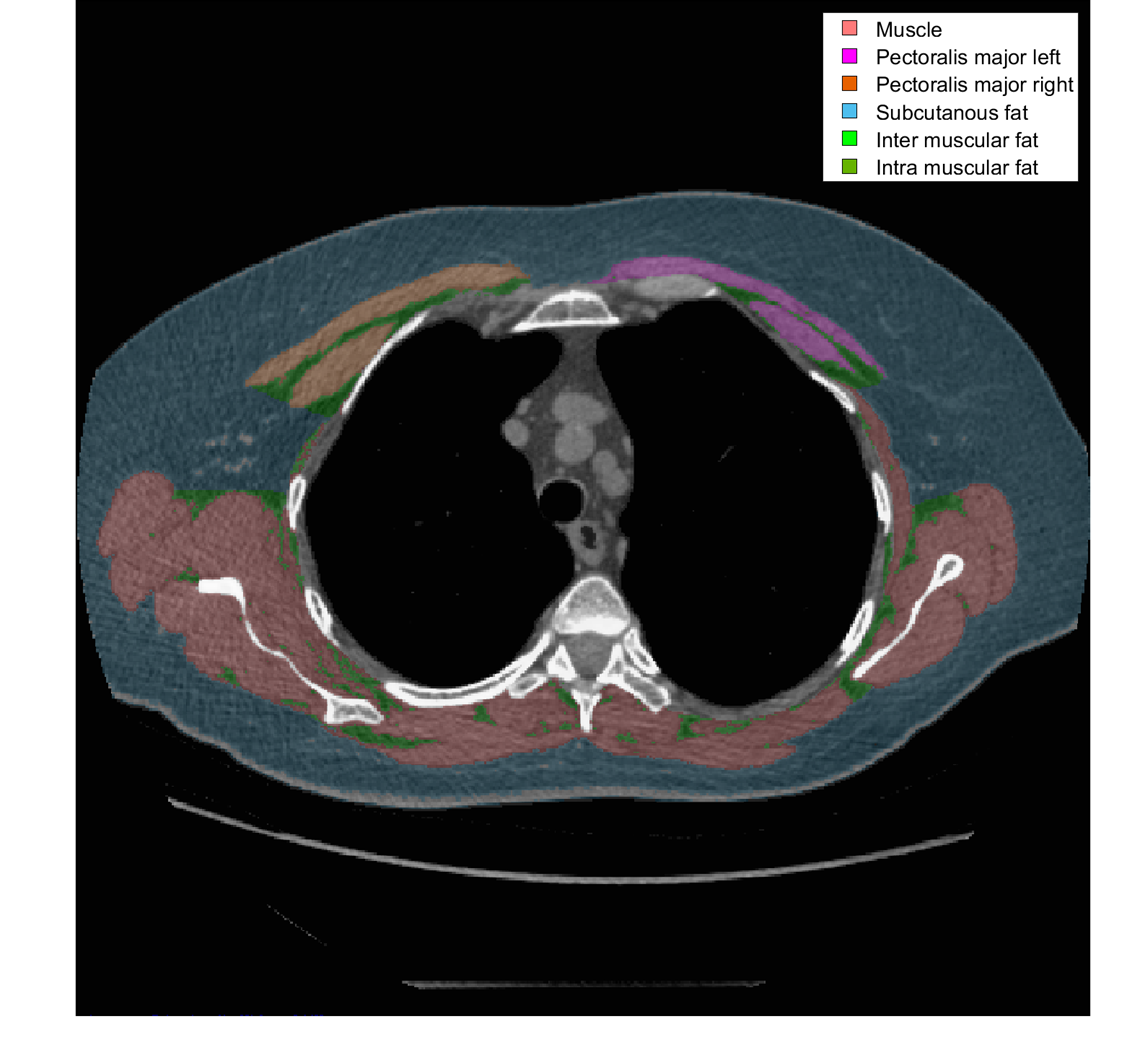

Derfor vil jeg gerne undersøge om man kan bruge i forvejen eksisterende undersøgelser af patienter som Computer Tomografi (CT) til potentielt at kunne fange patienterne tidligere i deres sygdomsforløb og opstarte rehabiliteringsforløb.

Det vil være muligt, da der foretages en række CT scanninger af patienter med KOL i løbet af deres sygdomsforløb som rummer mange flere oplysninger også om deres kropssammensætning som er uudnyttet. Således man vil kunne foretage en tidlig opsporing, samt måle om tiltagene er tilstrækkelige ved efterfølgende scanninger.

Inden for forskningsområdet om kropssammensætning anvender man oftest scanninger af maven, men hos patienter med KOL er scanningerne ofte begrænset til brystkassen.

Problemet er, at der på nuværende tidspunkt ikke findes en reference at holde målingerne af muskel og fedt fra brystkassen op imod ved CT scanninger med kontrast. Derfor arbejder jeg på dels at lave en reference for europæere med kontrast CT af brystkassen som tager højde for alder, højde og BMI, men samtidigt undersøger jeg også om inuit skal have deres egen reference baseret på eksisterende kontrast CT scanninger.